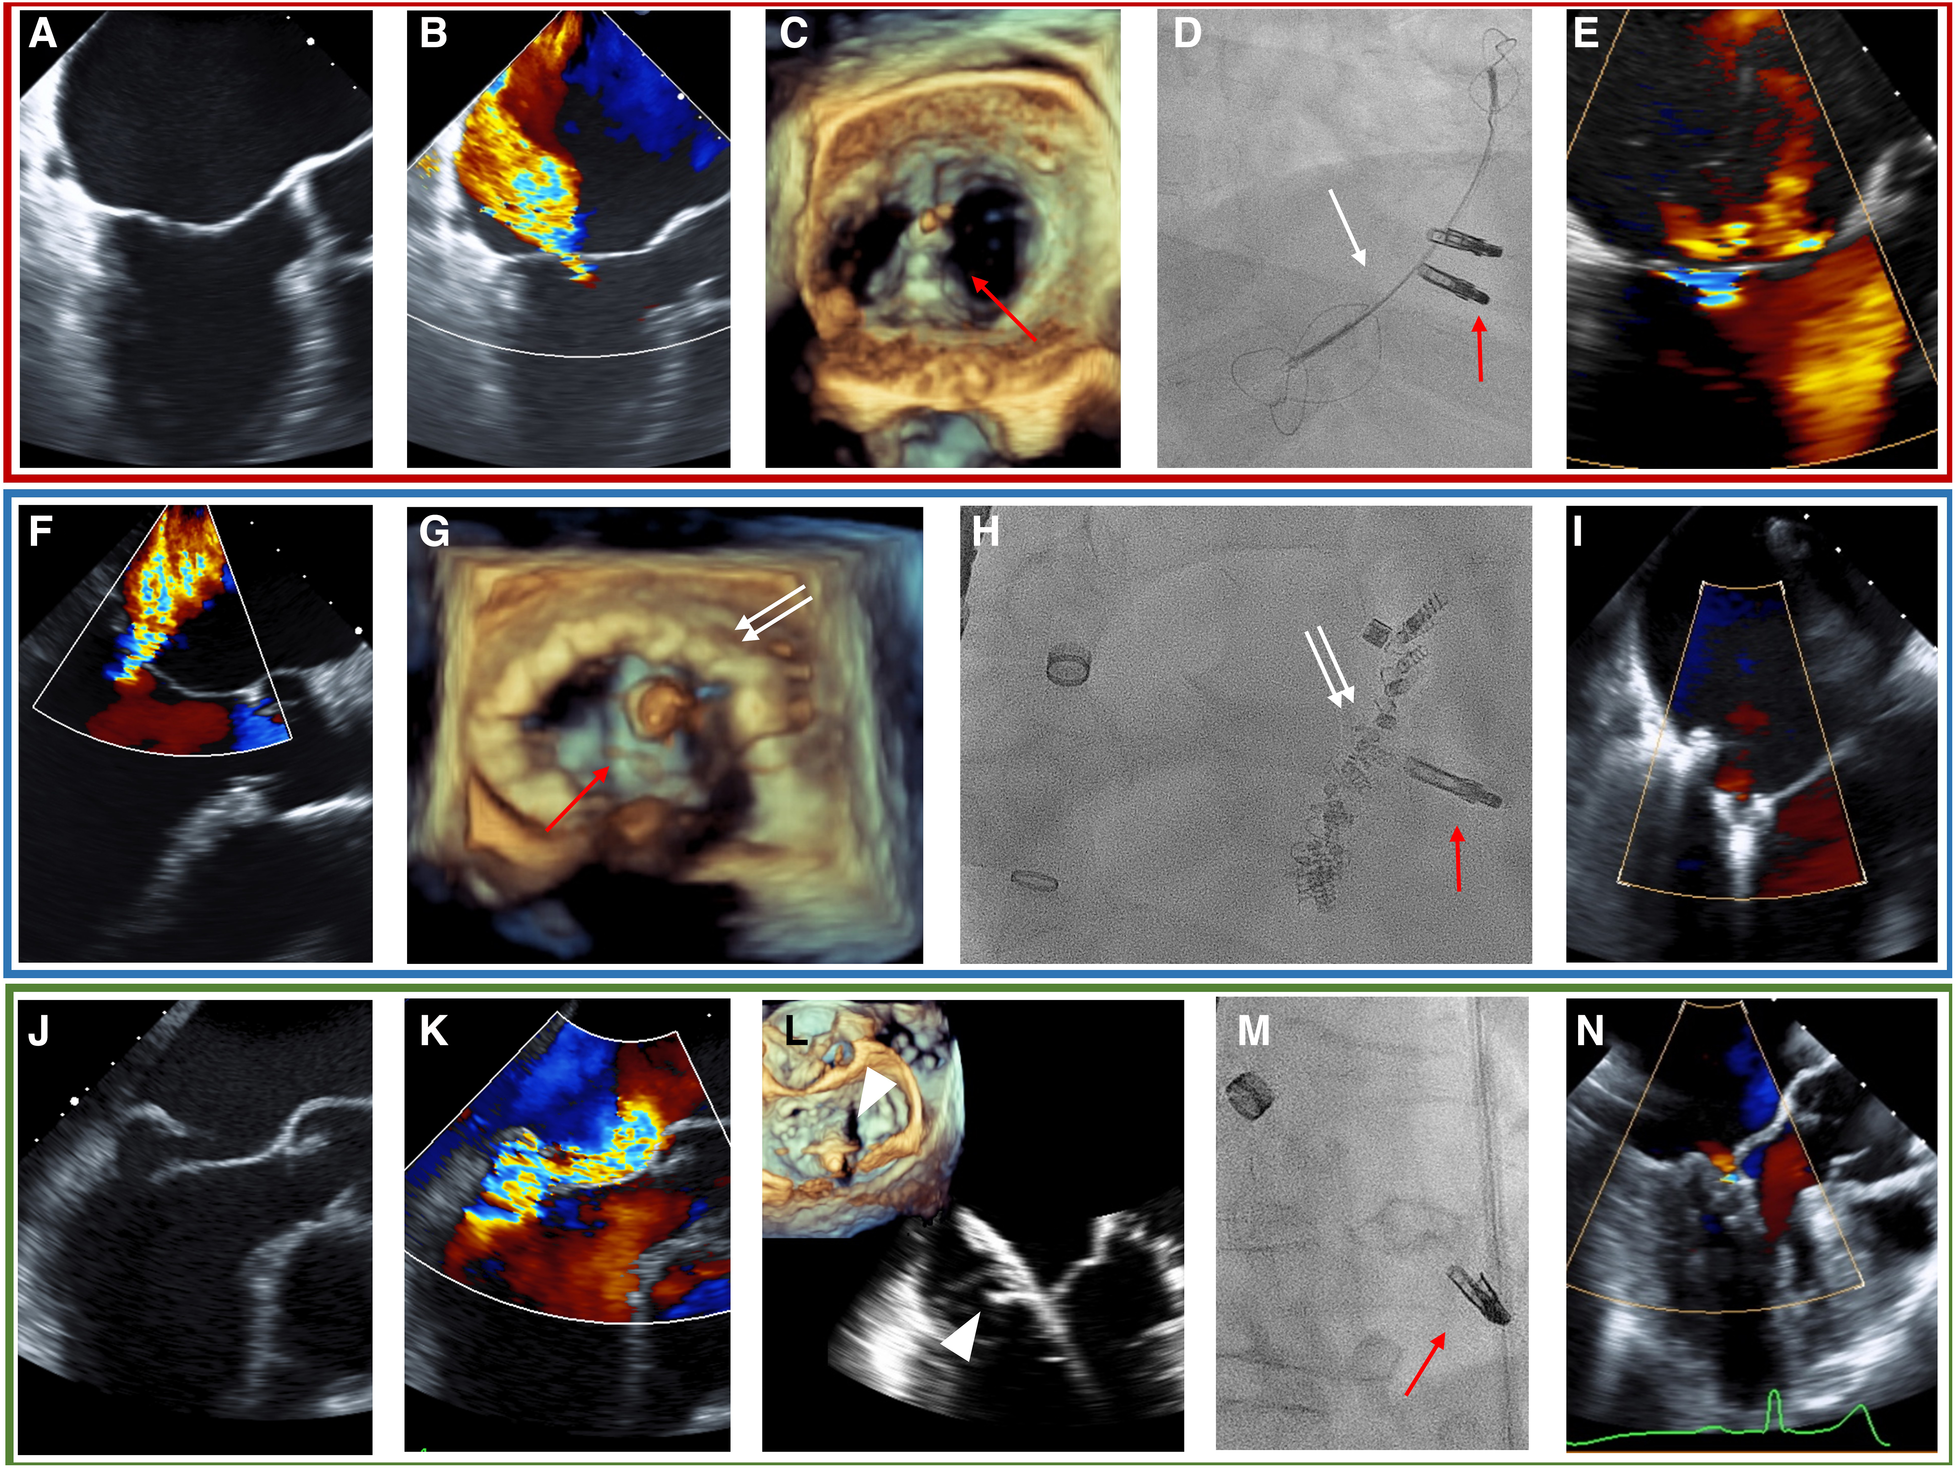

The Heart Team decided to recommend the transcatheter approach over a medical or surgical pathway in each patient. The Heart Team consisted of a cardiac surgeon, an interventional cardiologist, an interventional echocardiographer, and a cardiac anesthesiologist. The COMBO therapy was discussed as an option during the Heart Team deliberation in cases where treatment of the pathology by the dedicated device was deemed difficult, e.g., large mitral valve annulus in cases that were selected for transcatheter annuloplasty, or extended prolapse in cases selected for NeoChord implantation. This option was mainly put to discussion by both the interventional team, i.e., the interventional cardiologist and the interventional echocardiographer after the patient was considered unsuitable for cardiac surgery. The decision to employ COMBO therapy was ultimately made during the procedure at the discretion of the treating interventional cardiologist. In detail, during the procedures in the COMBO therapy group, the first procedure was performed as either CMCS (Figures 1A–E, red box) or Cardioband (Figures 1F–I, blue box) in patients suffering from SMR, or NeoChord (Figures 1J–N, green box) in patients with PMR caused by Prolapse and/or flail. Each procedure was then followed by M-TEER in the same session. The technical details of each procedure have been reported previously (17–22). All procedures were performed under general anesthesia using fluoroscopy and 3D transesophageal echocardiography (TEE) guidance in all cases.

Figure 1

TEE and fluoroscopy (D, H, M) of the representative cases for each COMBO therapy using M-TEER (red arrow) with either the CMCS (white arrow) in SMR (A–E, red box), Cardioband (white double-arrow, blue box) in SMR (F–I), or NeoChord (white triangle, green box) in PMR due to posterior leaflet prolapse (J–N). (A) Tenting shows SMR. (B) Baseline MR. (C) 3D-echo imaging during procedure. (D) Fluoroscopic image during procedure. (E) Post-procedural MR. (F) Baseline MR in SMR. (G) 3D-echo imaging during procedure. (H) Fluoroscopic image during procedure. (I): Post-procedural MR. (J) Flail of posterior leaflet. (K) Baseline MR. (L) Grasping of posterior leaflet with NeoChord. (M) Fluoroscopic image during procedure. (N) Post-procedural image of MR with TEE.